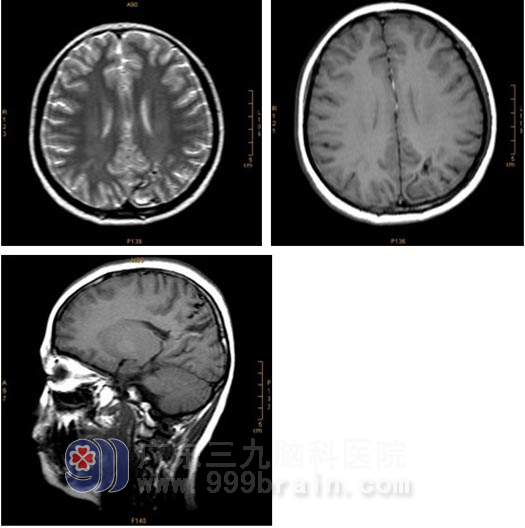

影像学(MRI+MRA)检查:

X-刀治疗前:左顶叶示片状异常信号影,T1WI呈低信号,T2WI以低信号为主,其内示小片状高信号影,FLAIR序列呈低信号,病变前上方示条状流空信号异常血管影。MRA显示左顶部可见畸形血管团影,左侧大脑中动脉远端增粗、延长并延伸至畸形血管团内。诊断:1.左顶叶动静脉畸形(左侧大脑中动脉参与供血);2.左顶叶脑出血后遗改变(软化灶形成、含铁血黄素沉着)。